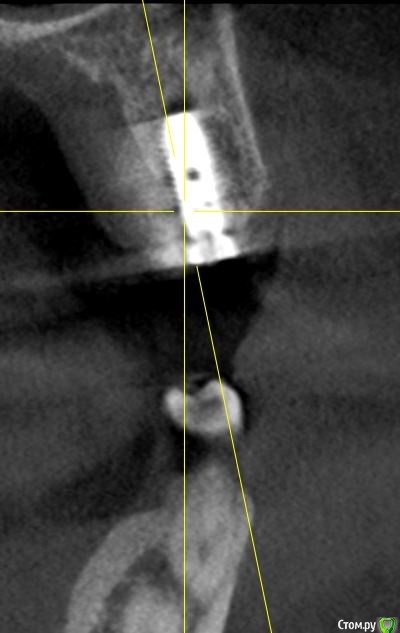

Irouil Опубликовано 29 сентября, 2020 Автор Поделиться Опубликовано 29 сентября, 2020 (изменено) По ориентации оси импланта на бугор антагониста я бы делал выводы о вестибулярном завале Не замерял сколько между ними, ну на глаз где-то 3 и есть Фото с винтами во рту нет, к сожалению, но ортопед рот тоже не смотрел, вердикт по снимкам Изменено 29 сентября, 2020 пользователем Irouil Ссылка на комментарий

Irouil Опубликовано 29 сентября, 2020 Автор Поделиться Опубликовано 29 сентября, 2020 Если включать перфекциониста, то есть незначительный завал, но это ж все нормально ортопедируется.Тут надо делить теорию и практику, на мой взгляд. Перкпучивать в человеке винты потому, что врач не хочет выключать перфекциониста - это не медицина, а IT или инженерия. С точки зрения практики А если говорить теоретически, то просмотрите на первый и последний предоставленные срезы: от зубов до винтов и между винтами минимально необходимые расстояния (замечу, что работа без шаблона), они между собой параллельны. Сдвигать корпусно 1.5 некуда - там вестибуло-медиальный корень 1.6 вестибулярно и дистально, а если убирать вестибулярный наклон - платформа выведет за пределы небной кортикалки. Если же двигать его корпусно вестибуло-медиально (чтобы не приближаясь к корню освободить пространство для небной ротации), то абсолютно идентичное движение должен совершить 1.4 - ровно в сторону корня 1.3. Получается, что единственное, что можно было бы подправить ТЕОРЕТИЧЕСКИ - немного сгладить медиальный наклон, но, опять таки, рискуя либо сближением с корнем 1.6 в пришеечной области, либо, что ещё хуже на мой взгляд, сближением с корнем депульпированного 1.3 в апикальной части. Так что это ещё тот вопрос - где и кто включает перфекциониста. На мой взгляд Ссылка на комментарий

Irouil Опубликовано 30 сентября, 2020 Автор Поделиться Опубликовано 30 сентября, 2020 А как он обосновал что нужно убирать винты? Слишком небно импланты, слишком сильный медиальный завал, слишком близко зубы Ссылка на комментарий

Дмитрий Л. Опубликовано 30 сентября, 2020 Поделиться Опубликовано 30 сентября, 2020 Вы как-то в дебри залезли. По-моему ортопеда просто смутил рисунок лунки) Что касается наклона: с такой ангуляцией нагрузка на винт действительно будет нерациональной, но всё не настолько плохо, чтобы проводить реимплантацию. Ссылка на комментарий

shy Опубликовано 30 сентября, 2020 Поделиться Опубликовано 30 сентября, 2020 коллеги , подскажите пожалуйста , что не так с ангуляцией? я просто совсем далек от ортопедии , но тут же градусов 6-10, при 15-20 + градусах делают цементную , насколько я знаю. 1 Ссылка на комментарий

Fin Опубликовано 30 сентября, 2020 Поделиться Опубликовано 30 сентября, 2020 (изменено) Слишком небно импланты, слишком сильный медиальный завал, слишком близко зубыВидимо док слишком замороченный в плане позиционированния. Решать по КТ конечно не правильно, посмотреть бы. Думаю доку прийдётся поработать с десной немного, а так можно и цементную и винтовую фиксацию реализовать. Да и тут не особо понятно, если вы при перестановке отступите от зубов подальше до между иплантами расстояния совсем не будет. С таким отношением коллеги Вы сами скоро слепки начнете снимать)) коллеги , подскажите пожалуйста , что не так с ангуляцией? я просто совсем далек от ортопедии , но тут же градусов 6-10, при 15-20 + градусах делают цементную , насколько я знаю.Поидее винтовая фиксация должна быть при условии что шахта не будет выходить на бугры или вестибулярно, иначе прийдётся пожертвовать эстетикой или бугром. Мультиюниты могут помочь сделать винтовую при больших углах (но не единичные коронки) или же шаровидная отвертка.Недавно на 15° абатменте делал винтовую виксацию при помощи шаровидной отвёртки, проблем не было. Изменено 30 сентября, 2020 пользователем Fin Ссылка на комментарий